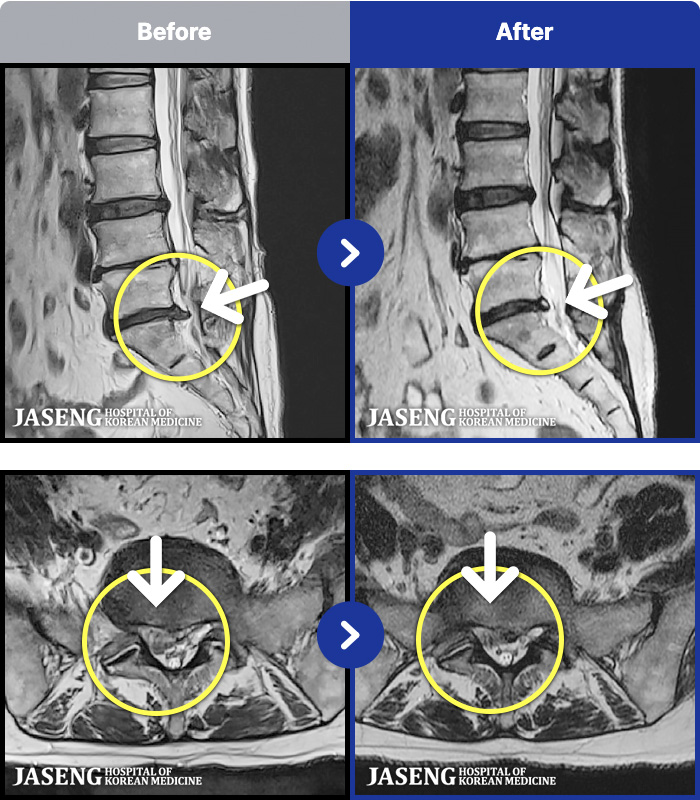

MRI ġ

MRI ũ ʸ Ȯϼ.